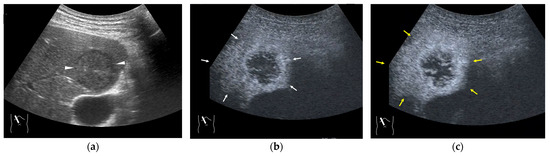

4.3. Budd–Chiari Syndrome

4.4. Hemodynamic Abnormalities in Liver Abscess

4.5. Hemodynamic Abnormalities in Liver Necrosis

4.6. Hemodynamic Abnormalities in Acute Cholecystitis